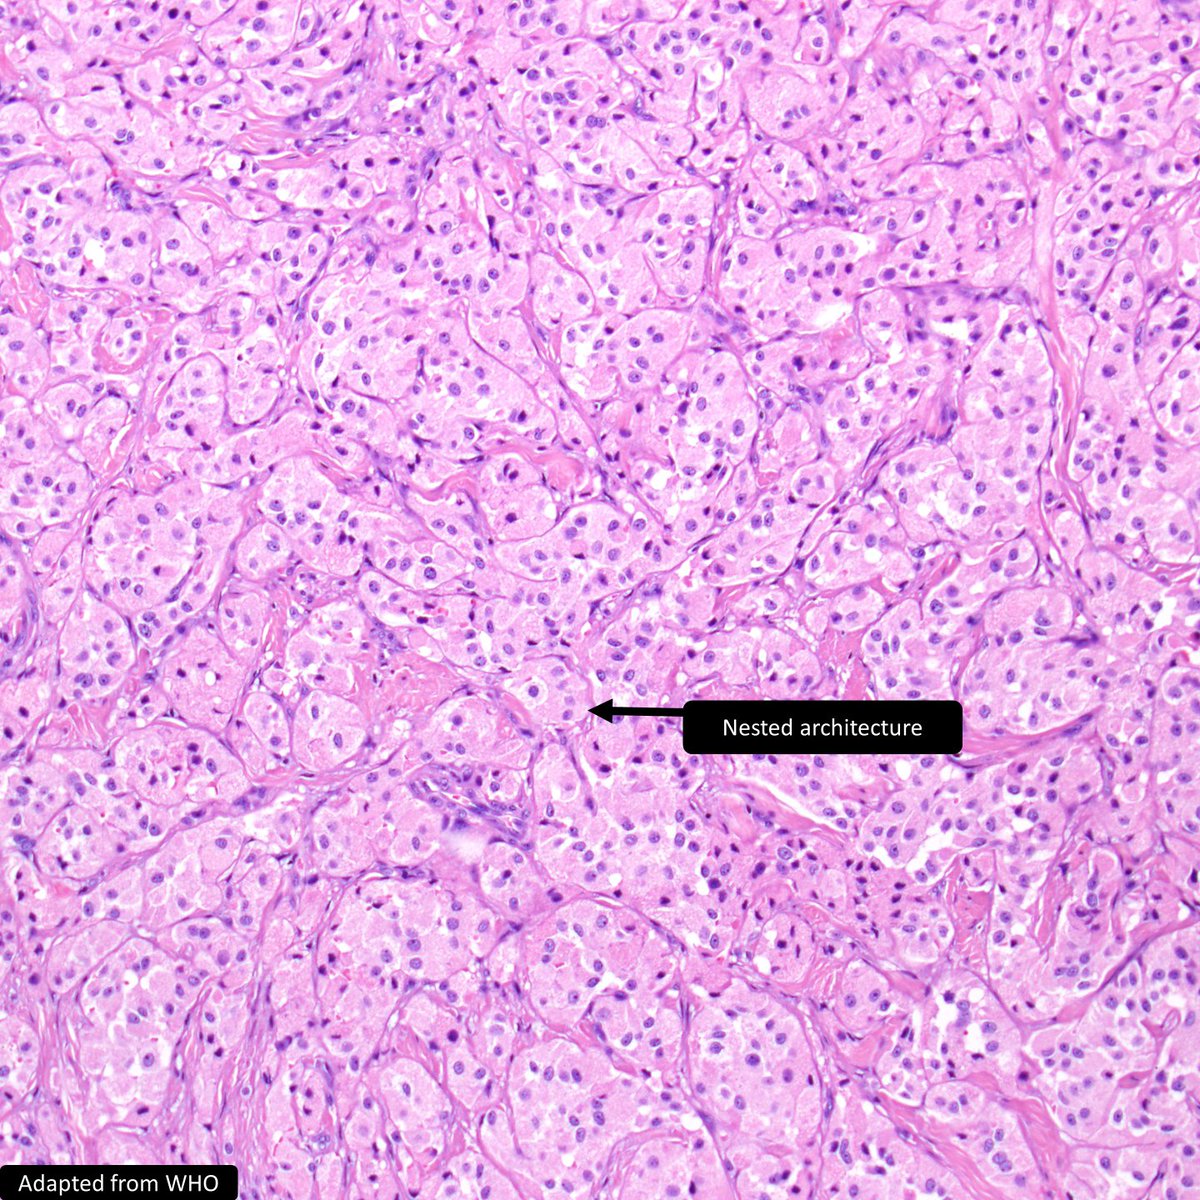

Clear Cell Sarcoma-like Tumor of the GI Tract ___ a) shows EWSR1 rearrangement b) has melanocytic differentiation c) usually affects older adults d) is most common in the stomach #GIPath #PathTwitter #Pathology